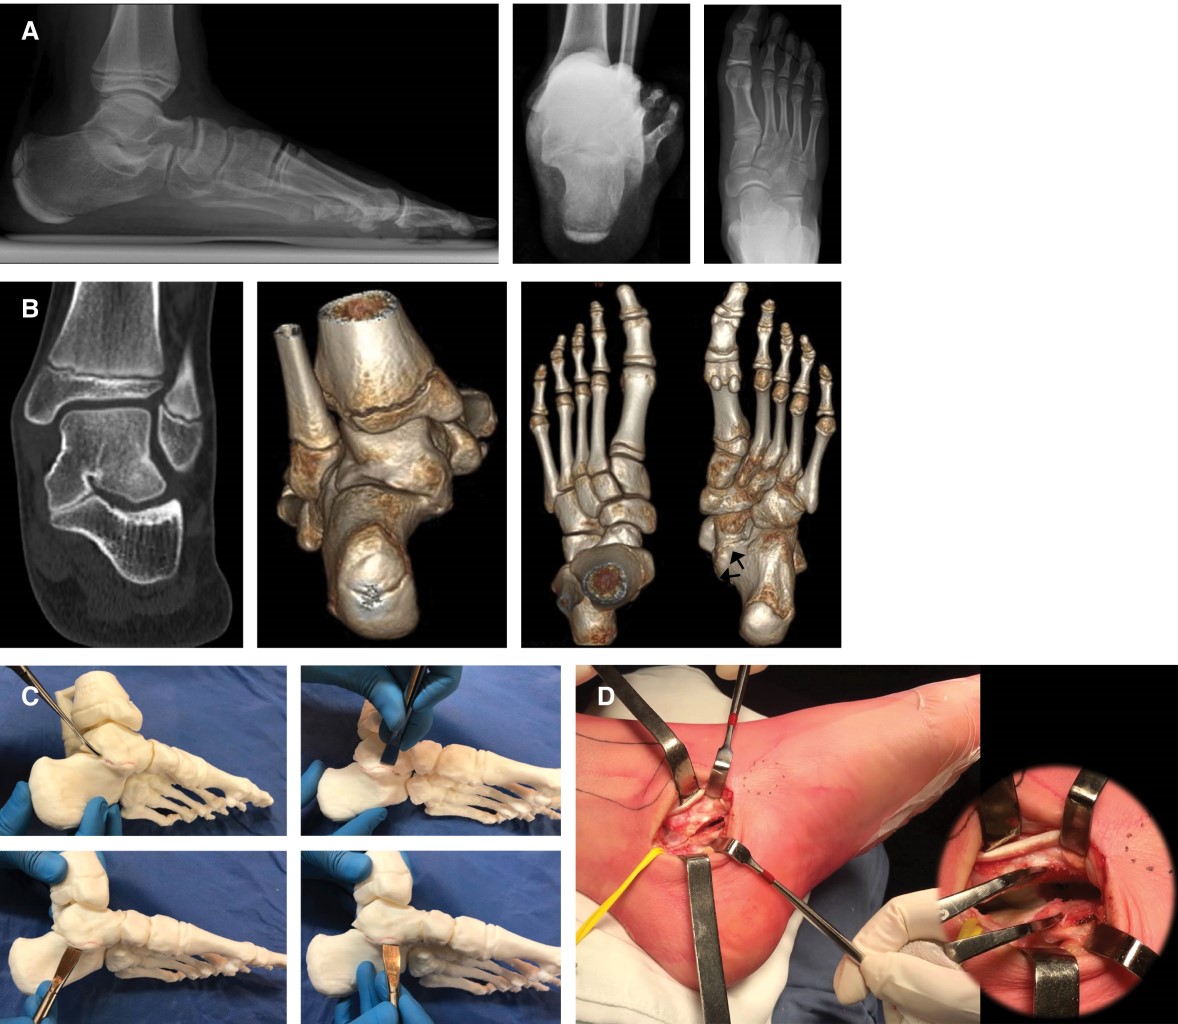

Three-dimensional biomodels for the surgical treatment of talo-calcaneal coalitions

Introduction: Surgical treatment of talocalcaneal coalitions (TCC) is challenging due to the high variability in clinical presentation and complex anatomy of the subtalar joint. The aim of this study is to describe our experience with the use of three-dimensional printing for pre-operative planning of TCCs. Material and methods: We prospectively studied patients with TCC treated between January 2017 to January 2019. Three-dimensional reconstructions were performed from tomographic images using the Mimics® 16 Materialize program. Preoperative planning was carried out with the 3-matic® Medical version 8 Materialize program. Subsequently, biomodels were manufactured in PLA (polylactic acid) with an FDM technology printer (fused deposition modeling) Ultimaker 3. The digital files were prepared for manufacturing with the Ultimaker Cura 3.6 program. Results: Five consecutive patients (6 feet) were evaluated. Average age was 13.2 ± 1.3 years. Five feet had not received prior surgical treatment, and one foot had a failed previous resection. The models were obtained at real scale (1:1 ratio). The impression of the biomodels allowed to determine precisely the involvement of the posterior facet, plane of resection of the coalition, magnitude of hindfoot deformity and, if necessary, to plan the osteotomies for realignment. Four feet had resection of the coalition associated to realignment, one foot had isolated resection, and one had a revision surgery (coalition resection). At the last follow-up, all patients were asymptomatic, and satisfied with the procedure. No patient required additional surgeries. Conclusion: The use of three-dimensional biomodels facilitates pre-surgical planning, allowing virtual planning to be translated into a more tangible one. Potentially, better quality planning could reduce surgery time and allow a more accurate correction of the deformity. Comparative studies are required to determine if these hypotheses are correct.

Figure 1